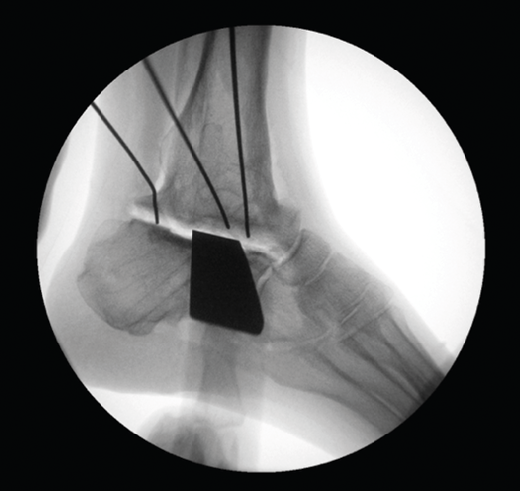

Figura 5. Control por radioscopia del aloinjerto.

- Tallado del injerto de manera intraoperatoria (Figuras 4 y 5).

- Resección intraoperatoria (Figura 8).